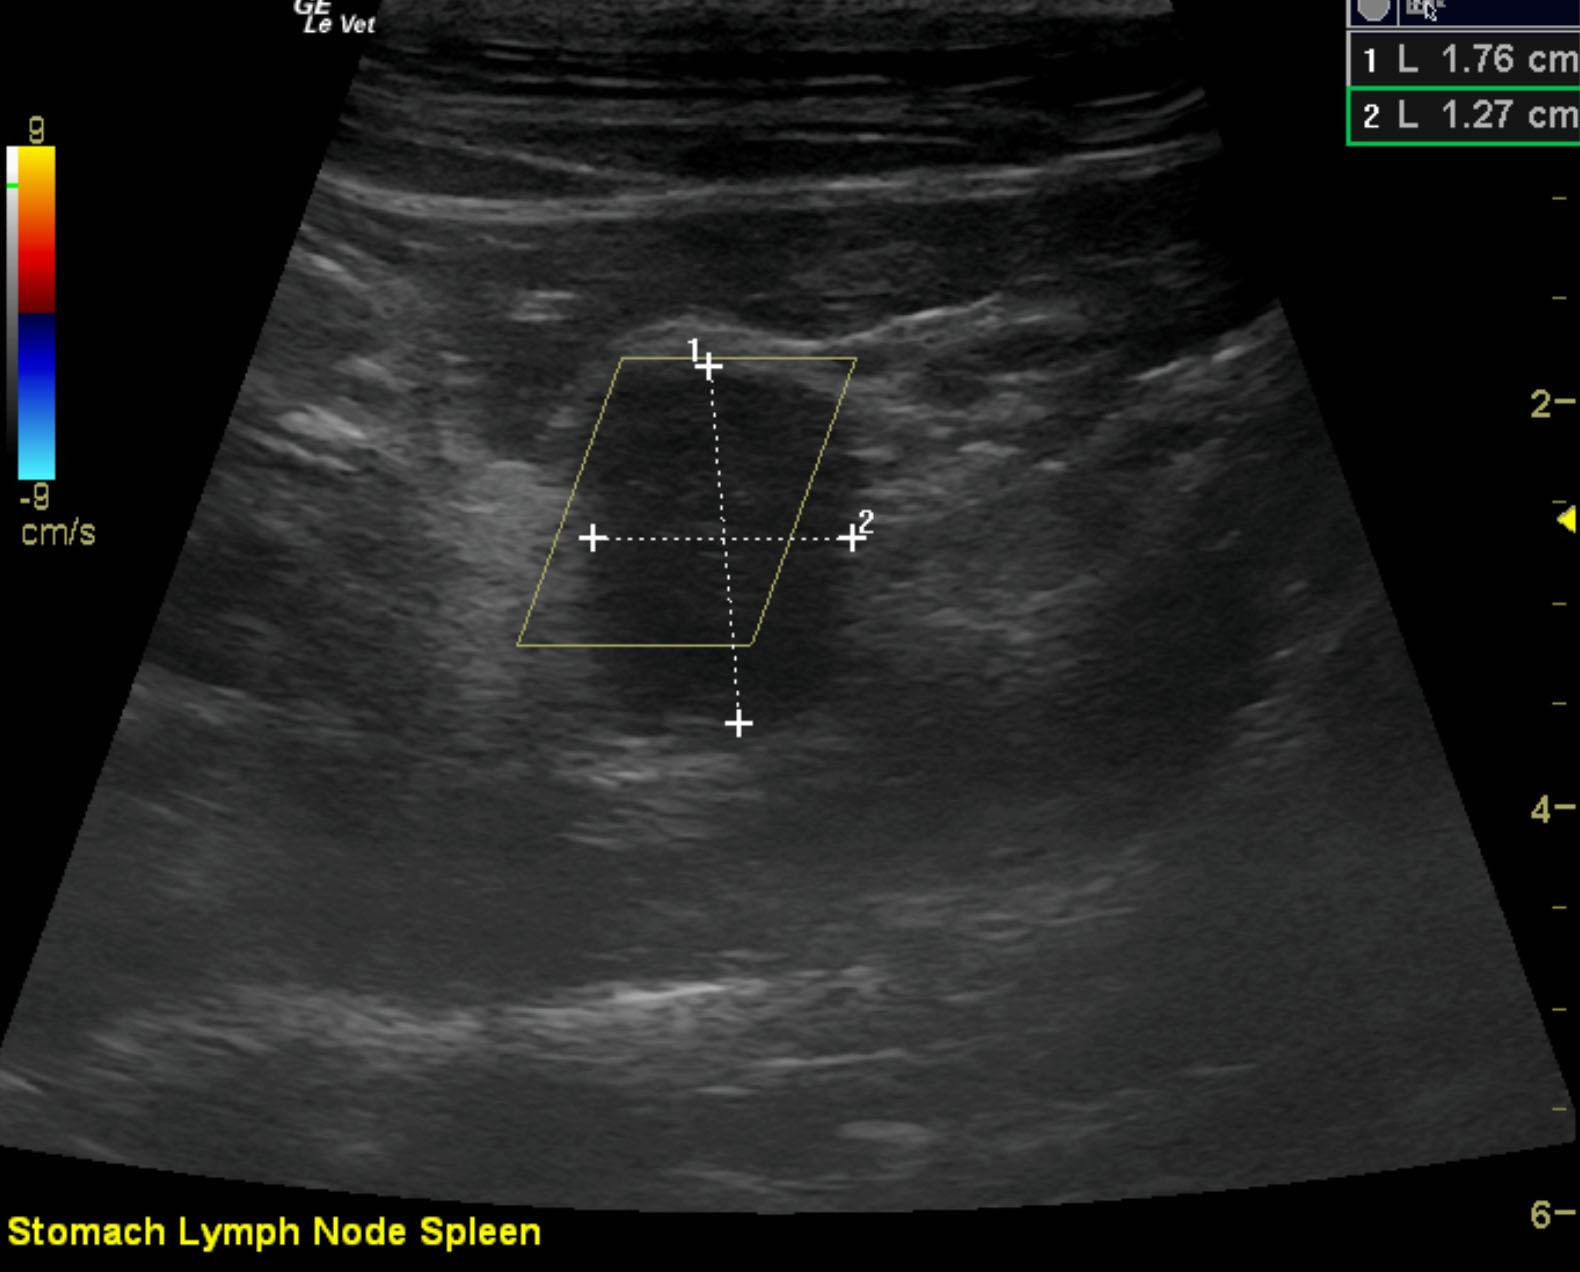

The patient is a feline DSH, NM, 14 years. The patient was hospitalized last week for pancreatitis, but specfPL remains elevated and has increased. The patient is now anemic and albumin is 2.2.